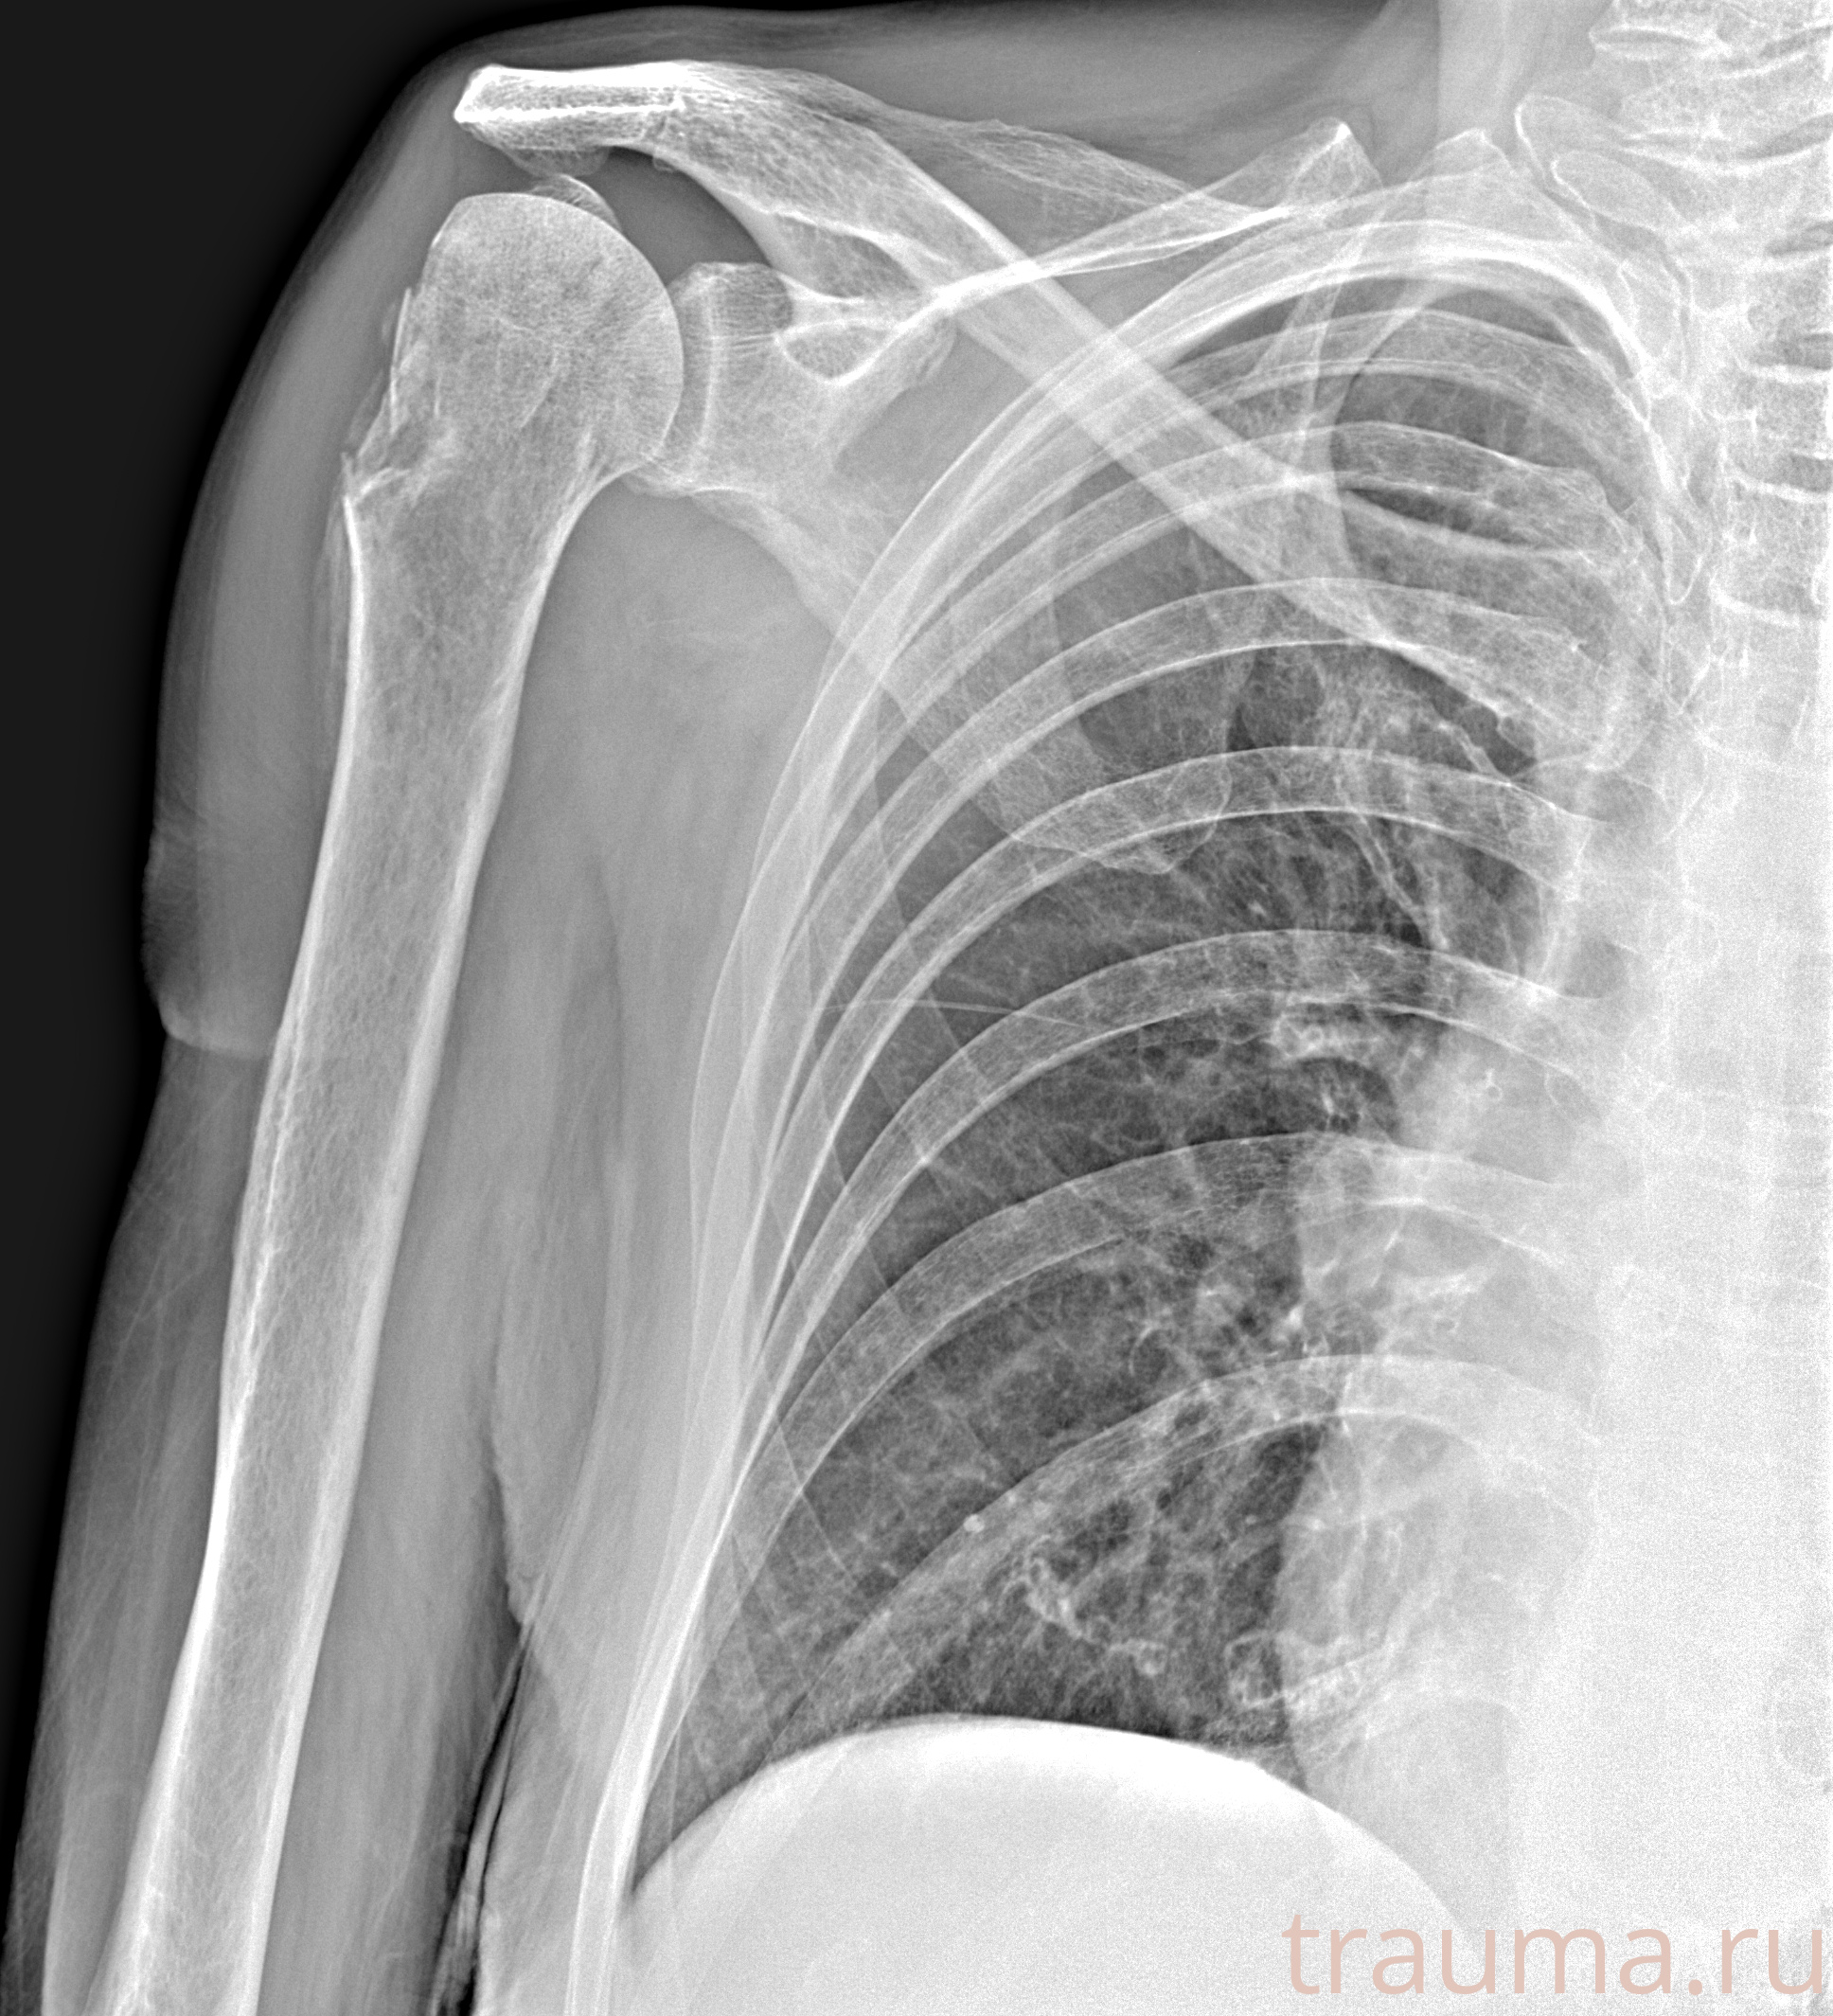

Рентгенограммы

Рентген на дому: по вашему адресу приезжает врач-рентгенолог, травматолог-ортопед с мобильным рентгеновским аппаратом, проводит диагностику травмы или заболевания, делает необходимые рентгенограммы, дает рекомендации по дальнейшему лечению. Получить качественные снимки в домашних условиях возможно благодаря уникальной методике, разработанной МосРентген Центром для института  Склифосовского